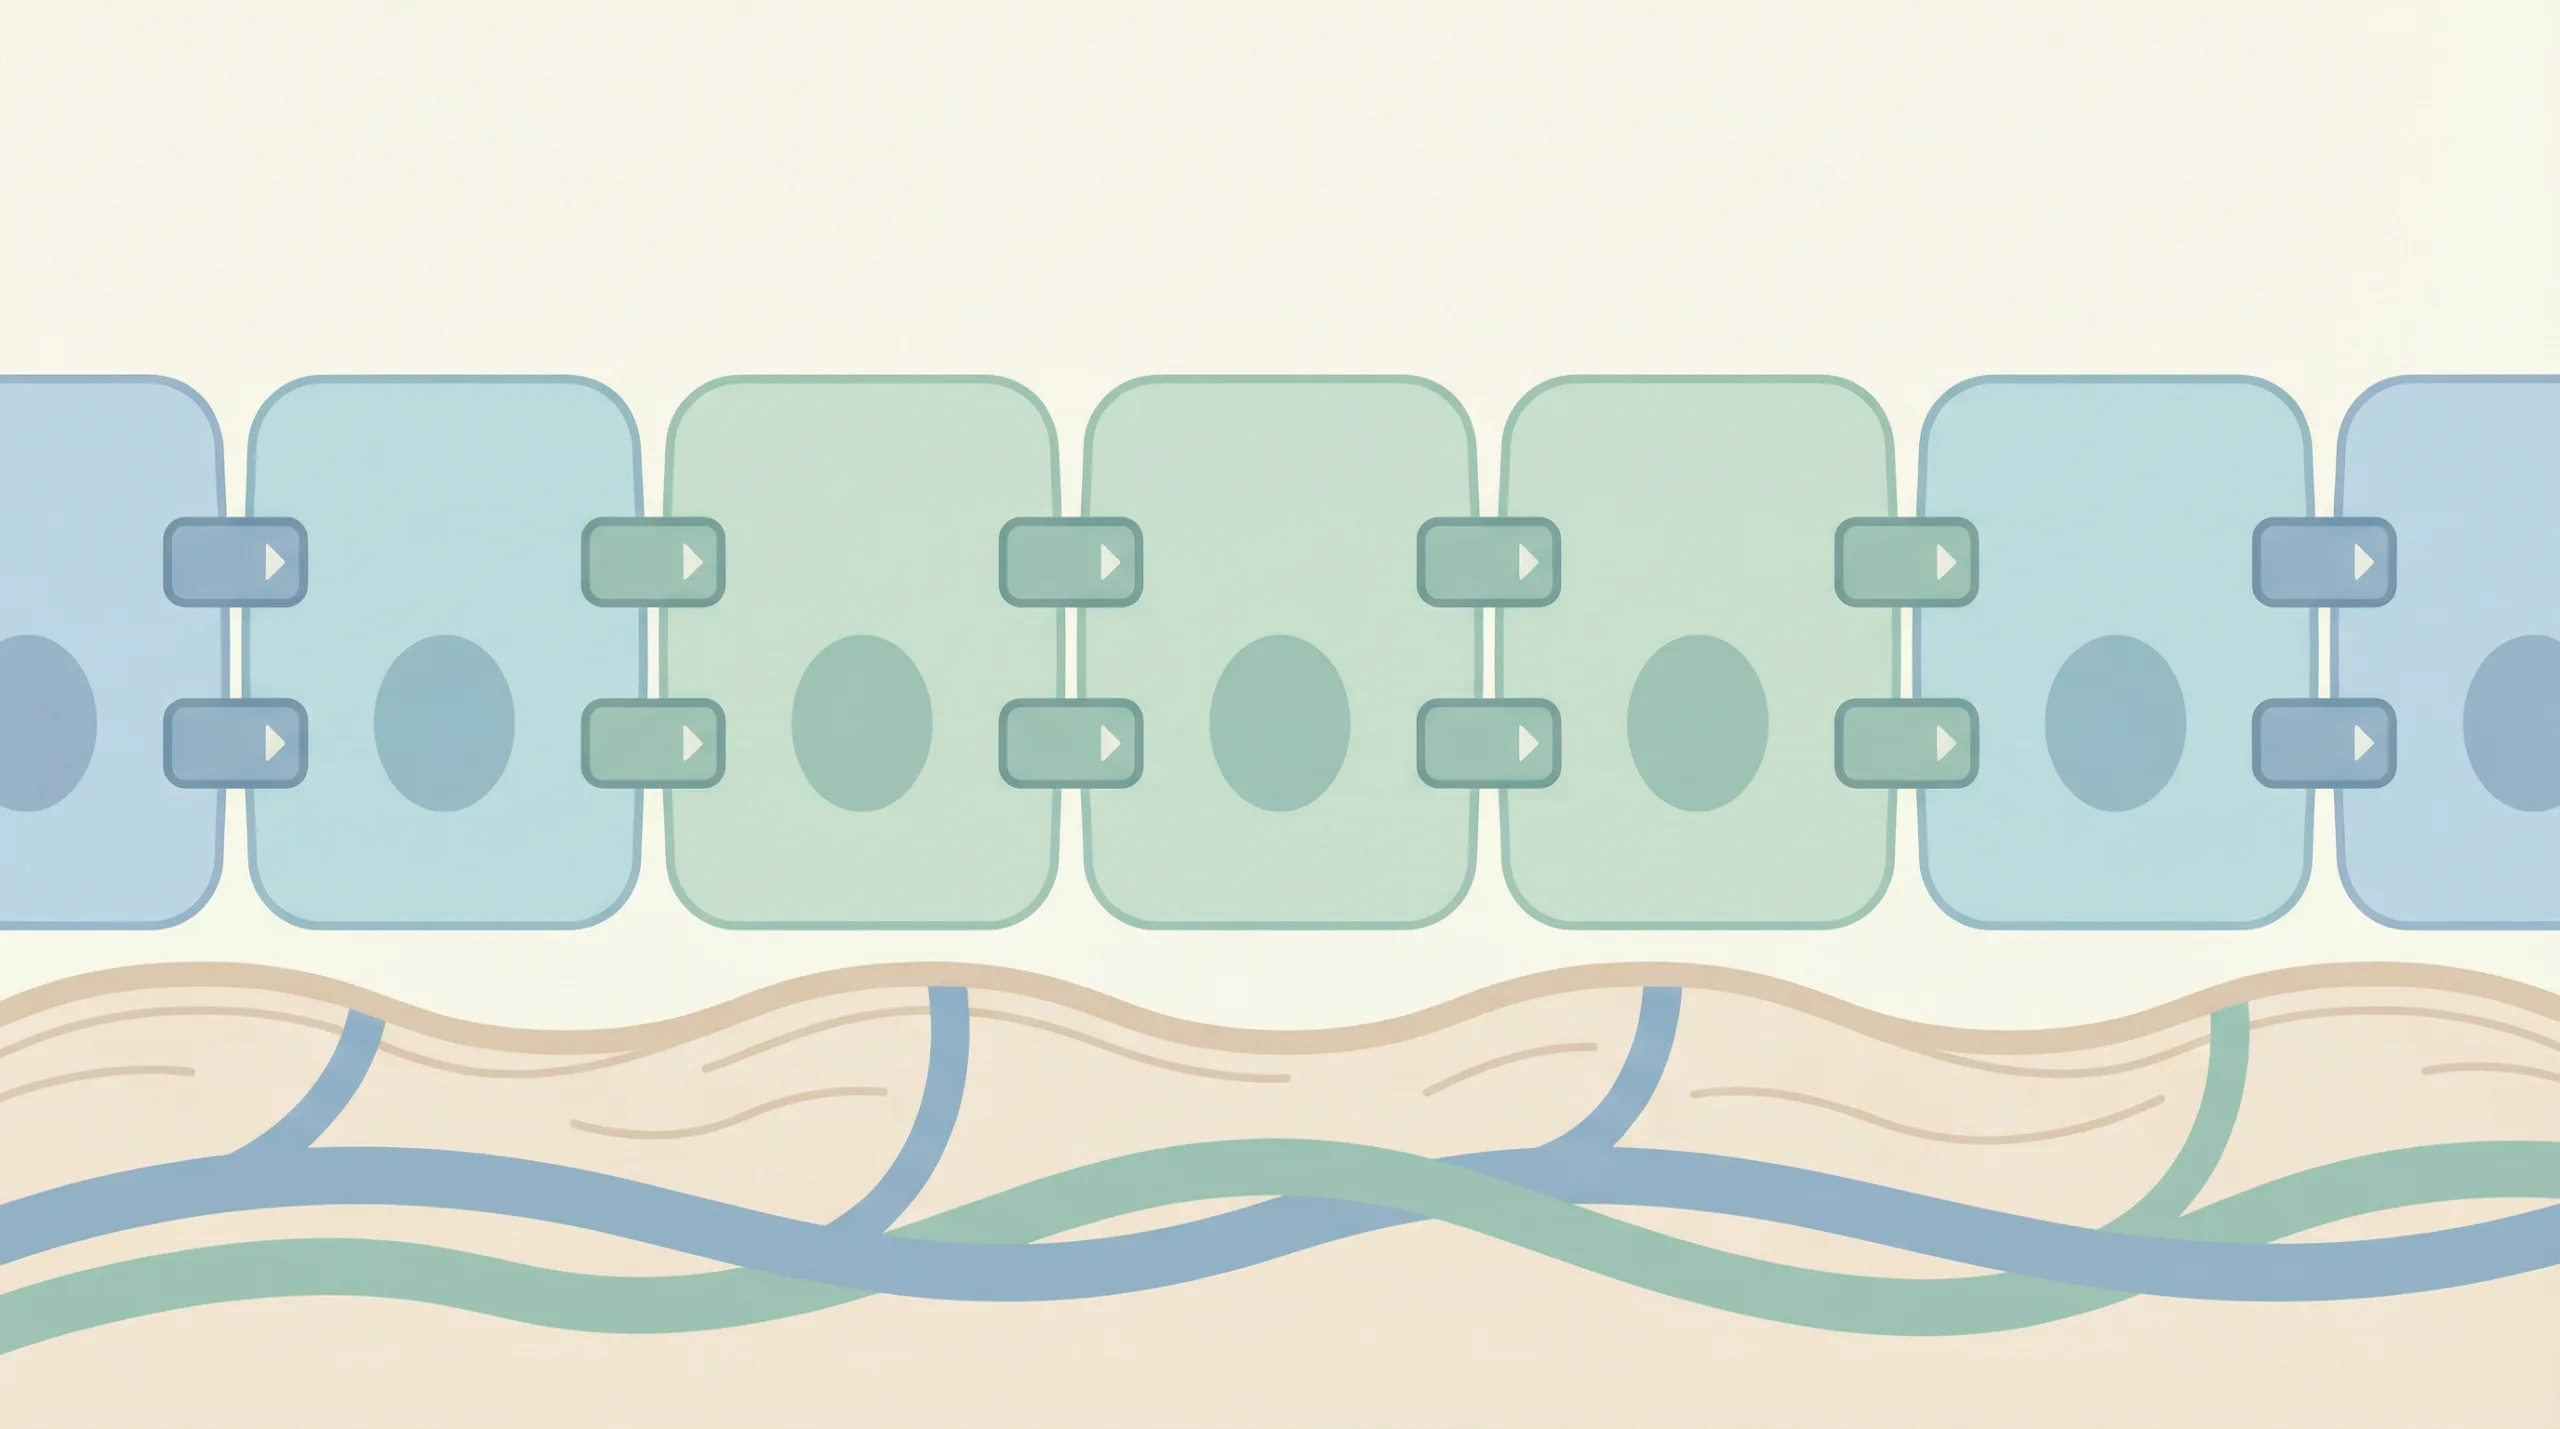

Infeksi usus merusak keseimbangan bakteri usus karena patogen bersaing untuk nutrisi dan memproduksi toksin yang membunuh bakteri baik. Lapisan pelindung usus (tight junction) juga bisa rusak sehingga zat yang tidak seharusnya masuk ke aliran darah bisa lolos. Tight junction, artinya ikatan protein antara sel epitel usus yang menjaga agar zat tidak bocor sembarangan ke aliran darah.

Riset di PubMed Central (2025) membuktikan kapasitas fungsional dan komposisi metabolit mikrobiom berubah drastis selama fase recovery dari infeksi enterik. Bakteri penghasil SCFA (short-chain fatty acids) menurun sementara bakteri oportunistik meningkat. Proses pemulihan infeksi usus butuh waktu 2-12 minggu tergantung keparahan dan antibiotik yang digunakan.

Probiotik seperti Lactobacillus dan Bifidobacterium membantu memulihkan kolonisasi bakteri baik, memperkuat tight junction, dan mengurangi peradangan pasca infeksi usus. Strain tertentu seperti Saccharomyces boulardii bahkan terbukti mengurangi risiko diare terkait antibiotik. Prebiotik (serat larut) memberi makan bakteri baik sehingga mereka bisa berkembang kembali. Review di PubMed Central (2025) menyatakan strategi restorasi mikrobiom setelah antibiotik atau infeksi meliputi probiotik, prebiotik, dan diet serat tinggi untuk mendukung pemulihan usus.

Pemulihan bakteri usus pasca infeksi usus biasanya 2-8 minggu. Lapisan mukosa dan tight junction bisa membutuhkan 4-12 minggu untuk kembali optimal tergantung keparahan dan penggunaan antibiotik.

Studi di PubMed Central (2025) menemukan komposisi metabolit mikrobiom berubah secara dinamis selama fase recovery. Gen resistensi antibiotik dapat menetap di bakteri tertentu meski infeksi sudah sembuh, sehingga menjaga pola makan sehat dan probiotik jangka panjang membantu mengembalikan ekosistem usus ke kondisi baseline. Konsistensi diet serat dan probiotik selama 8-12 minggu memberikan hasil terbaik untuk pemulihan infeksi usus secara menyeluruh.